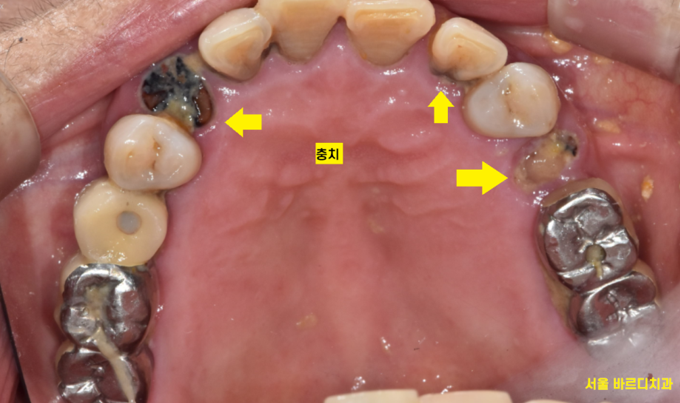

임플란트 머리 빠진 것 뿐만 아니고

전반적으로 치료는 필요했습니다.

다른 부분도 충치도 있고

뿌리만 남은 게 있어서

그 사이 다른 부위 충치 치료도 하고..

여기저기 충치도 있고

뿌리만 남아있었는데 싹~ 치료하신 모습을 보니

뿌듯합니다.

깔끔해졌습니다.